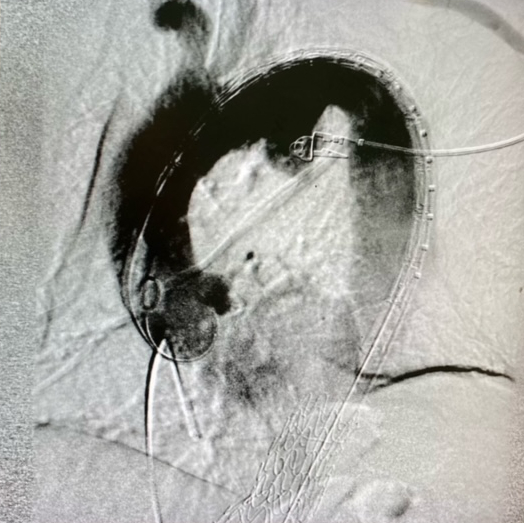

Un foro di pochi millimetri praticato all'altezza dell'inguine, senza incisioni chirurgiche o procedure invasive potenzialmente stressanti, ha consentito all’équipe della Chirurgia vascolare ed endovascolare dell'Ospedale di Chieti di impiantare su un paziente, per via percutanea (senza taglio), un’endoprotesi aortica custom-made, ovvero costruita su misura.

Il paziente, 73enne, era affetto da aneurisma in prossimità del cuore, causato da un’ulcera che aveva indebolito la parete dell’aorta.

Era stata posizionata un’endoprotesi toracica, ovvero un tubo di rivestimento interno nel torace, pungendo l'arteria femorale all'inguine, senza tagli, navigando internamente nelle arterie.

“Dopo aver studiato il caso clinico nella sua complessità - spiega nel dettaglio il dottor Fiore -, abbiamo optato per l'impianto di un’endoprotesi progettata su misura per il paziente che potesse evitare la sternotomia e la sostituzione di tutto l’arco dell’aorta, previo bypass delle arterie del collo.”

“Abbiamo – prosegue Fiore – posizionato l'endoprotesi attraverso un foro di pochi millimetri praticato all'altezza dell'inguine, senza incisioni chirurgiche. L'intervento è stato possibile grazie all’”Aortic team” del Dipartimento Cuore della Asl Lanciano Vasto Chieti, che prevede la discussione del caso clinico tra chirurghi vascolari, cardiochirurghi, cardiologi e radiologi interventisti: una collaborazione che apre la strada a nuove tipologie di trattamento innovative, in grado di trattare patologie a elevatissima mortalità in tempi brevi e con un rischio di complicanze bassissime. La degenza del paziente è stata di appena cinque giorni”.